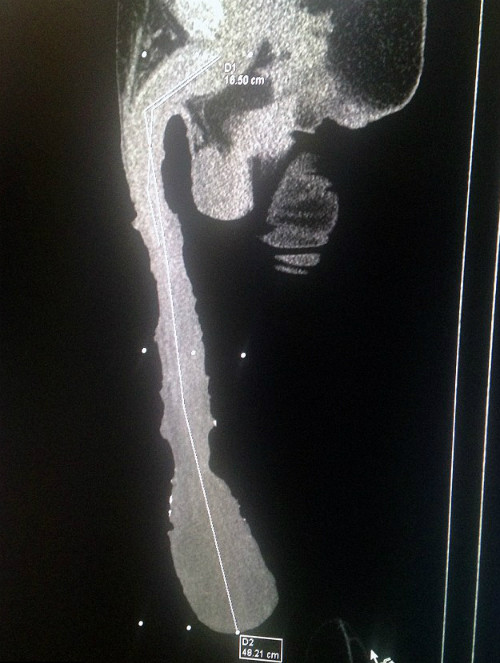

"Cậu nhỏ" bất thường cũng khiến ông đối mặt với những vấn đề nhiễm trùng đường tiết niệu do nước tiểu không thoát hết khỏi bao quy đầu. Các bác sĩ đã kiểm tra bằng máy quét và xác định kích cỡ thật của dương vật chỉ khoảng 18 cm, còn lại phần lớn là bao quy đầu và máu.

| Các bác sĩ đã kiểm tra và xác định chiều dài dương vật phần lớn là bao quy đầu. Ảnh:Men's Health. |